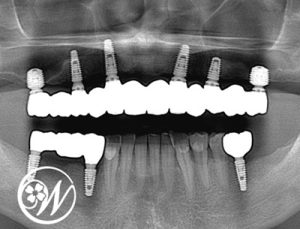

④ 最終補綴(ジルコニア)

治癒を確認後、最終的なかぶせ物を作製しました。

・最終補綴:ジルコニア

・固定方法:スクリュー固定(上顎・下顎とも)

上部構造お取り付け後